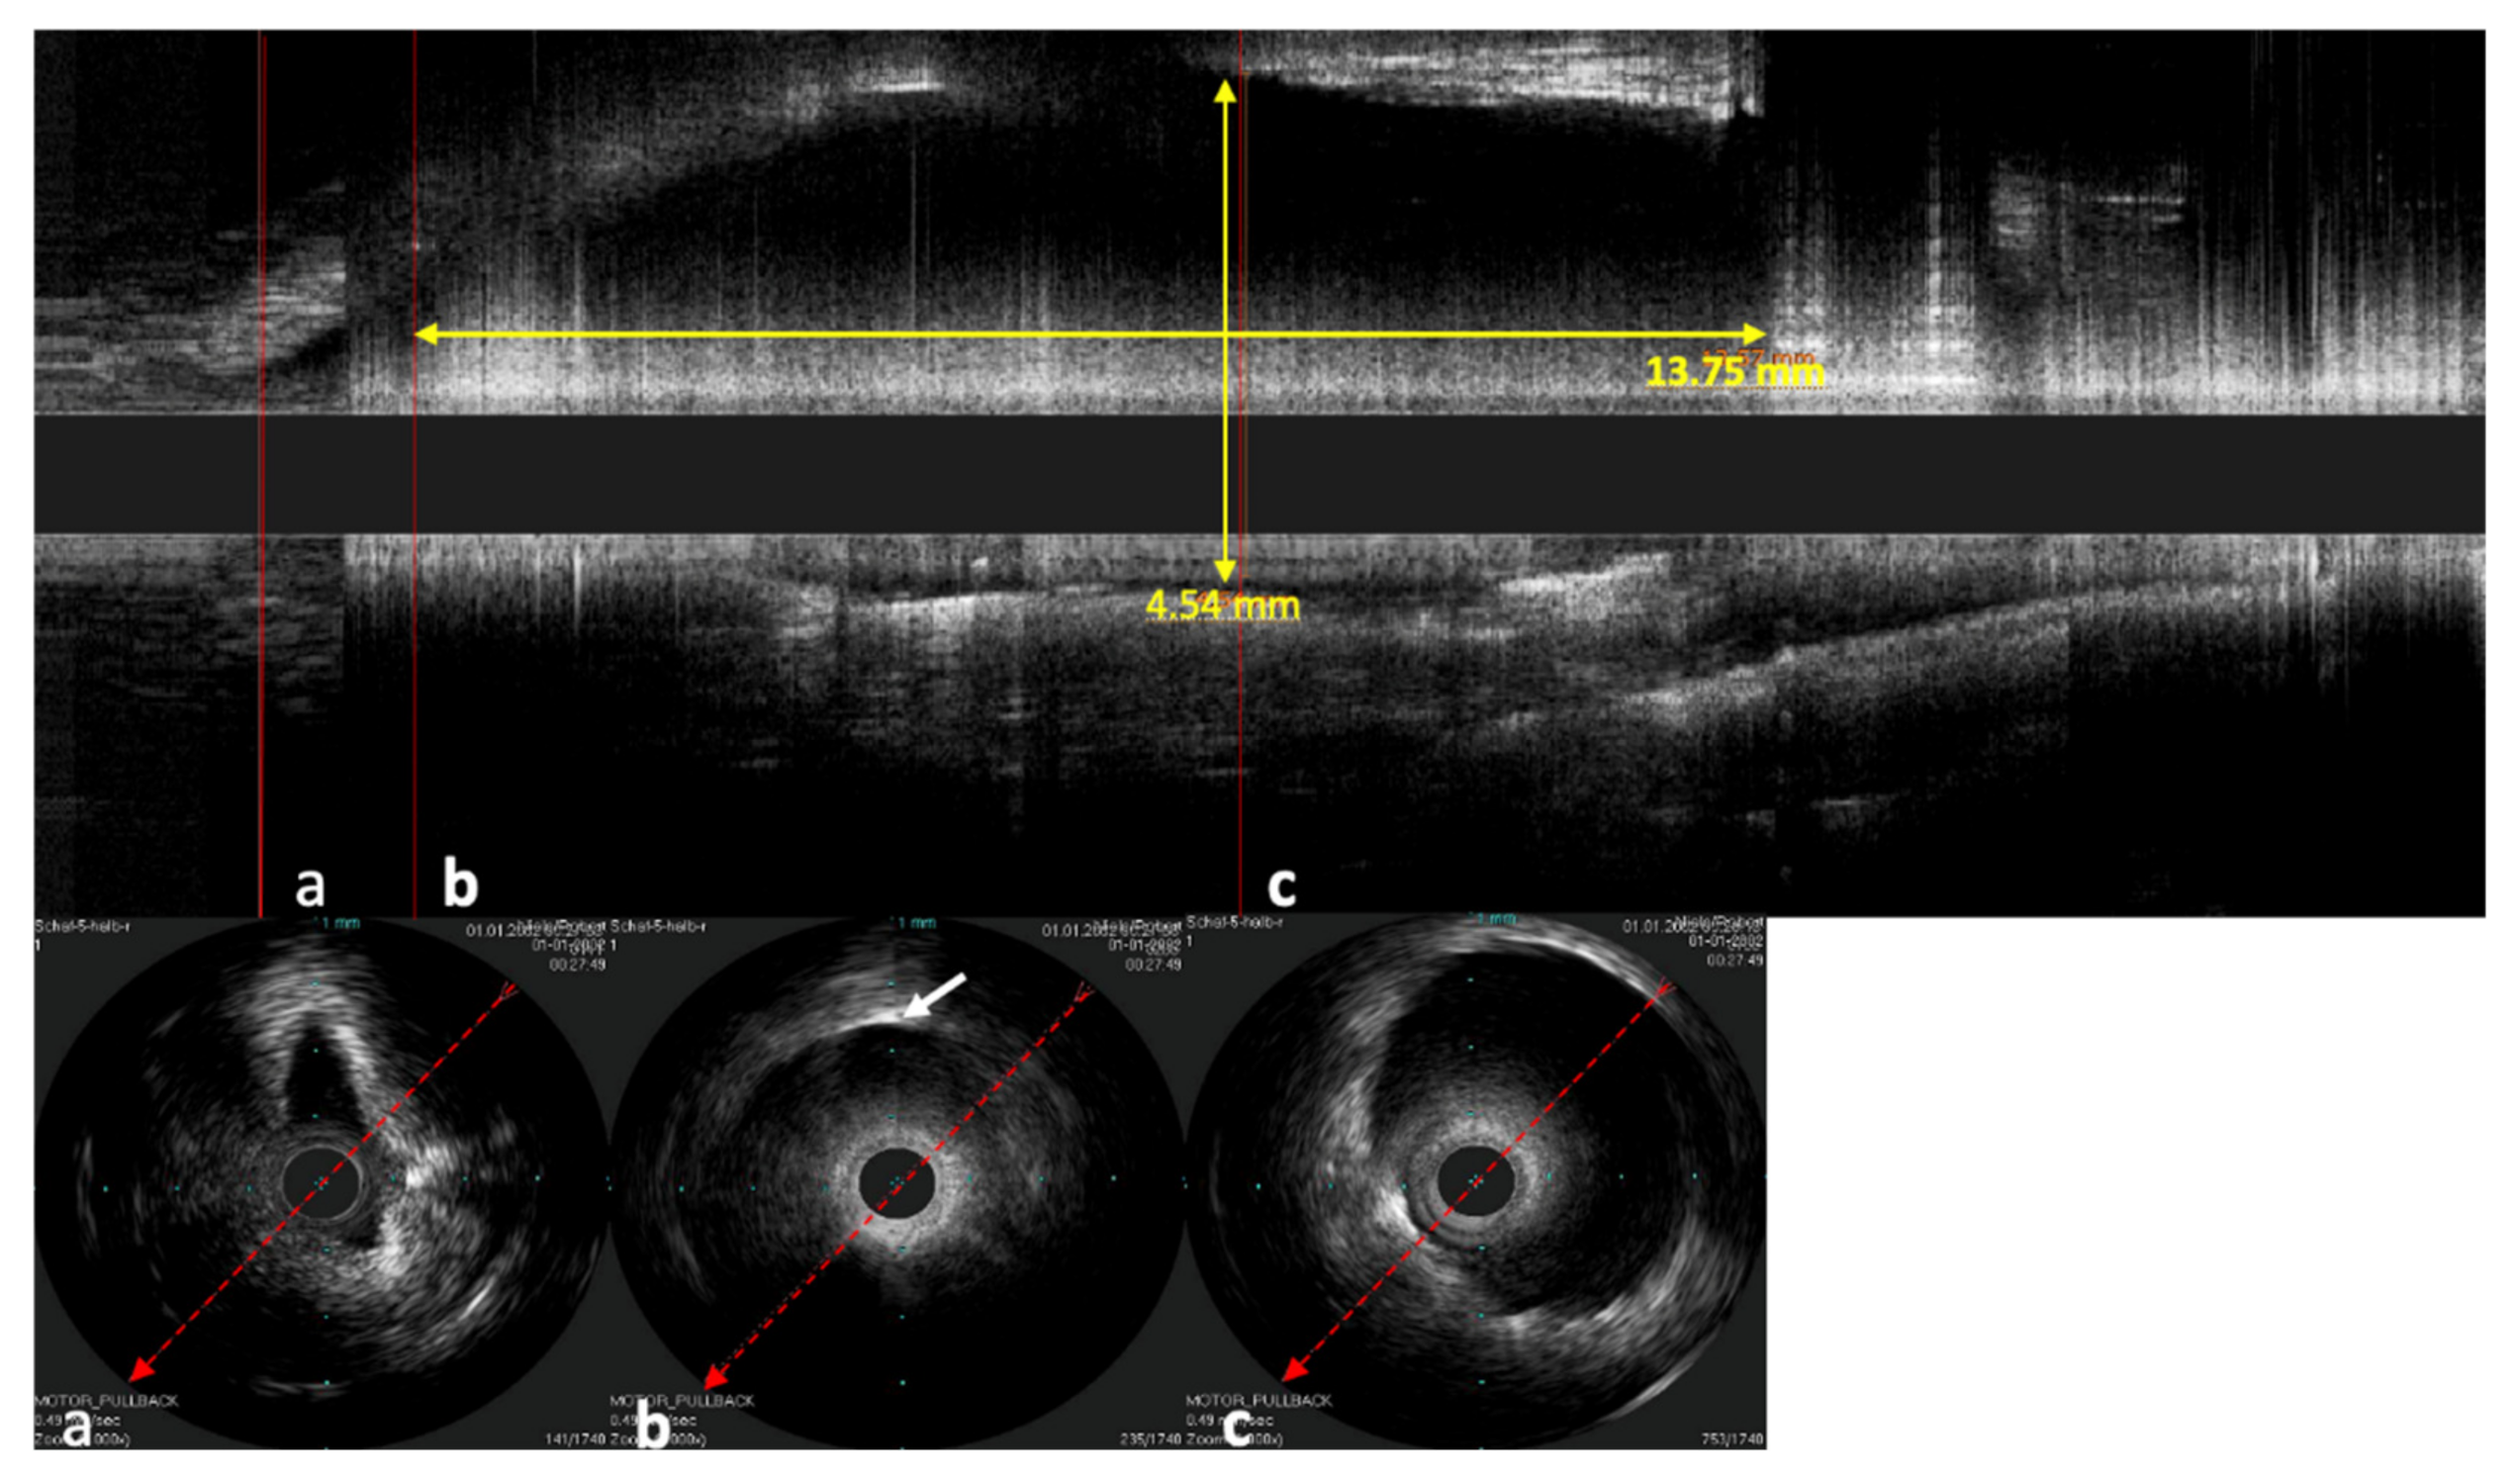

The stent inside of the ET was visualized by the echogenic metal struts of the stent and the widened lumen (Figure 7).

In the longitudinal view, not only can the stent shape be investigated but also how the mucosa of the ET lies around the stent and the position of the stent in the lumen of the ET (Figure 8). In one case, the catheter was next to the stent and not inside of the stent lumen. The stent struts were clearly visible next to the probe in the ultrasound image. Damage to the probe or the stent could not be detected in this case.

Figure 7. Ultrasound image of the stented ET. The lumen of the ET is opened by the unfolded stent. The IVUS probe is located in the lumen of the stent. The stent struts can be seen echogenically, and sonic extinction is marked with white arrows. Note: the ET was flooded with water before the scan to allow for sonic coupling.

Figure 8. Sonographic image of the stented ET, performed with the Refinity ST probe. The upper image shows the longitudinal view of the scan. Parts (ac) show the respective cross-sections of the scans. Part (a) shows the area in front of the stent, where the tubal lumen widens toward the stent. Part (b) shows the initial area of the stent where the first stent strut can be seen sonographically (indicated by white arrow). Part (c) shows the cross-section in the middle section of the stent. The cross-section here was measured to be 4.54 mm. In the longitudinal view, a length of 13.57 mm was measured.